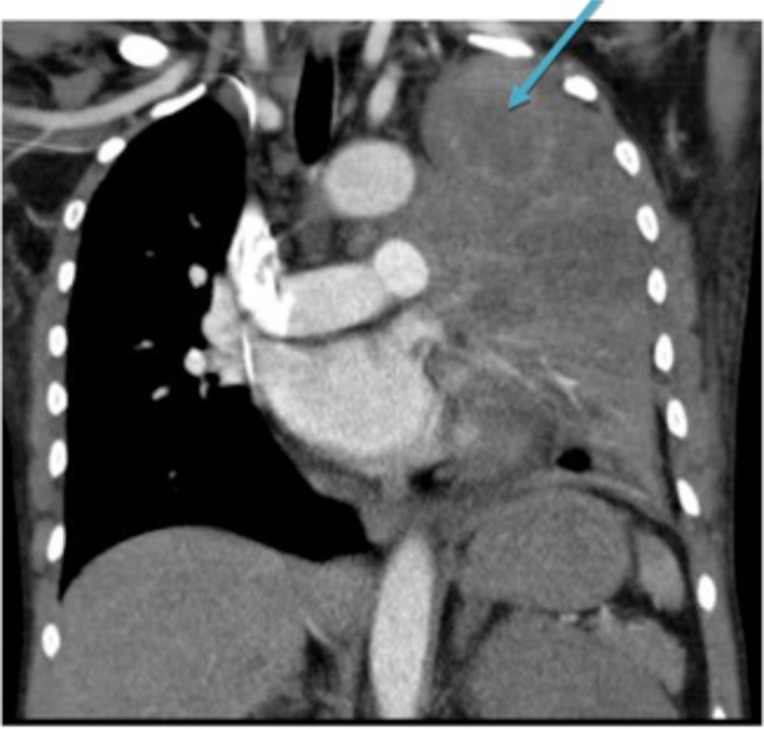

我们报告了一例47岁的非裔美国女性,她有15包年的烟草使用和大量酒精使用,表现为关节炎,并被发现有阳性的抗核抗体(ANA)、抗双链DNA抗体(抗dsdna)和抗干燥综合征相关抗原a和抗原B(抗ssa和抗ssb)。她随后被发现有肺腺癌合并肥厚性肺骨关节病(HPO)。这是一例肺腺癌患者的抗核抗体阳性和关节炎,可被误诊为系统性红斑狼疮。

We present a case of a 47 year-old African American female with 15 pack-years of tobacco use and heavy alcohol use who presented with arthritis and was found to have a positive antinuclear antibodies (ANA), anti double stranded DNA antibodies (anti-dsDNA), and anti-Sjogren's syndrome-related antigen A and antigen B (anti-SSA and anti-SSB). She was subsequently found to have a lung adenocarcinoma associated with hypertrophic pulmonary osteoarthropathy (HPO). This demonstrates a case of positive antinuclear antibodies and arthritis in a patient with lung adenocarcinoma, which can be falsely diagnosed as systemic lupus erythematosus.